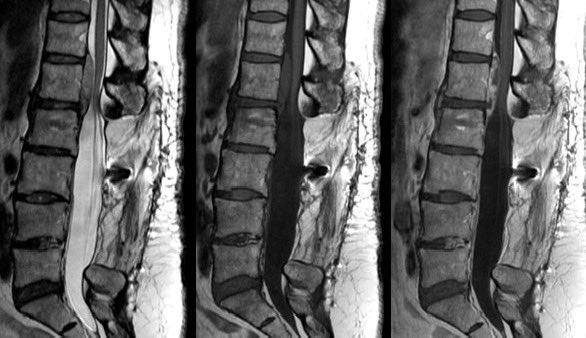

Elderly female. No interventions. New bilateral lower extremity weakness. Thoughts regarding this finding?

RJ tweet mediaRJ tweet mediaRJ tweet mediaRJ tweet media